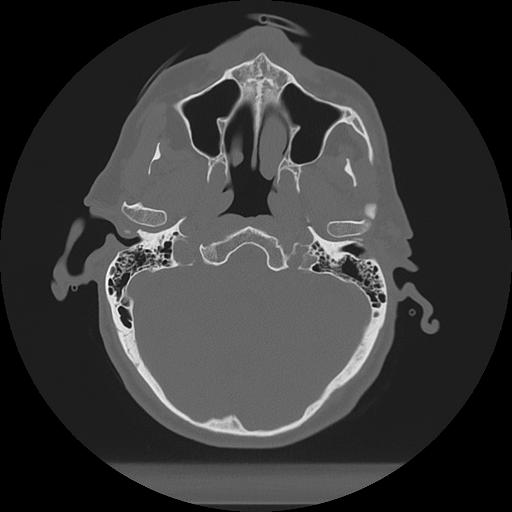

11 HUESO,,Axial,2.0,HUESO,,